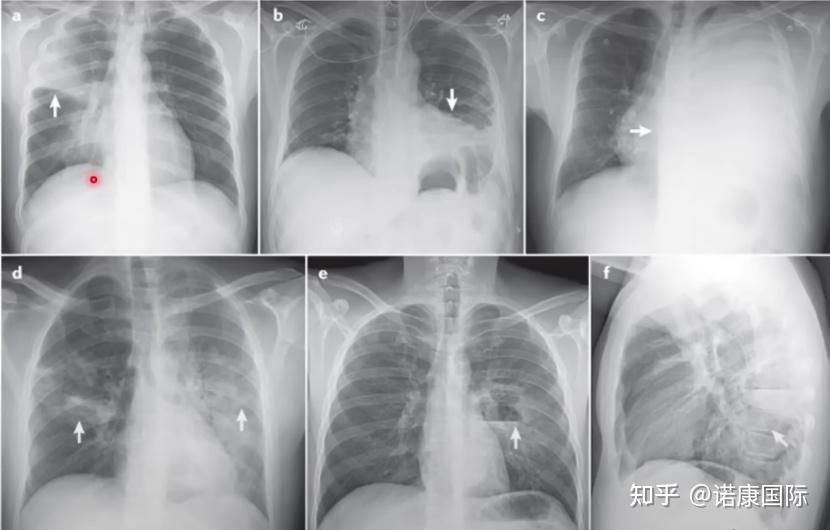

又见白肺,一文教你如何跟患者讲解平片,收藏!!!_积液

图片尺寸640x680